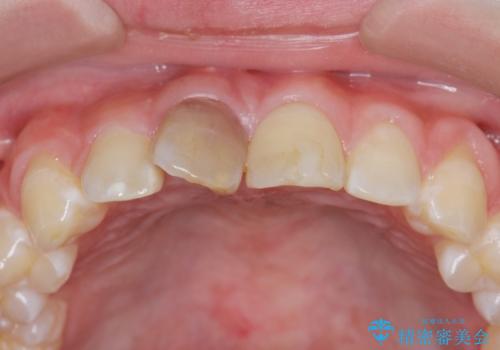

前歯をきれいにしたい ジルコニアクラウンによる審美治療

- 前歯の見た目の改善を求めて来院されました。

ジルコニアクラウンによる審美性の改善を計画します。

失活歯のため捻転を改善し、根管治療は特に希望されなかったのでそのままとしました。

今回失活歯であったため捻転を取り反対側の前歯に揃えて補綴を行うことができました。